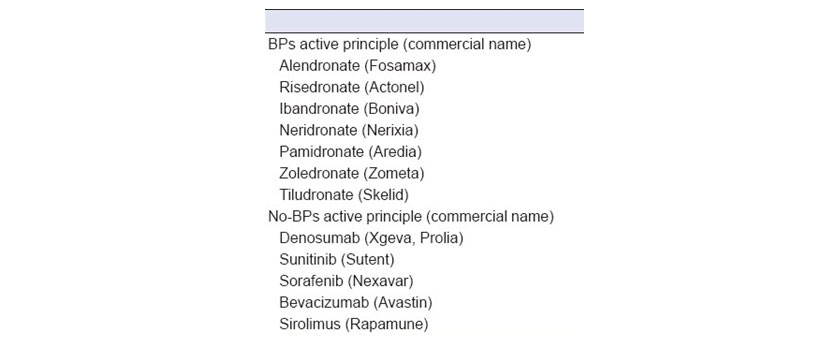

Los BF orales se usan para tratar afecciones que incluyen osteoporosis, osteopenia, osteogénesis imperfecta y enfermedad de Paget. Los atirresortivos como el inhibidor del ligando RANK (denosumab) detiene la función de los osteoclastos, reduce la resorción ósea e intensifica la densidad ósea. Los medicamentos antiangiogénicos inhiben el desarrollo de nuevos vasos sanguíneos al detener la cascada de señalización de la angiogénesis. Los exámenes orales y la terapia adecuada son esenciales para disminuir el riesgo de ONM en pacientes actualmente tratados con bifosfonatos, antirresortivos o antiangiogénicos o antes de iniciar la administración. El tratamiento de los ONM es un desafío importante y el protocolo de tratamiento aún no se ha establecido. Por lo tanto, la prevención es esencial.

Rosella D, et al. Realizó una investigación con el objetivo de evaluar el nivel de conocimiento de los estudiantes de odontología acerca de los medicamentos relacionados a la osteonecrosis. Se realizó un cuestionario a 98 estudiantes. 99% de los participantes declararon conocer los BF, pero solo el 34.8% de los estudiantes conocían la definición correcta de ONM. Casi todos los estudiantes identificaron la importancia de informar en la anamnesis, el uso de los BF, así como de controlar a los pacientes antes del comienzo del tratamiento; por otro lado, el conocimiento sobre cómo realizar un adecuado tratamiento dental invasivo en pacientes bajo tratamiento, no fue adecuado. Además, la mitad de los estudiantes no reconoció ningún principio activo o nombre comercial de BF. La situación era aún peor con respecto a las drogas alternativas involucradas es decir antirresortivos o antiangiogénicos (29%).

Figura 4: Principales fármacos relacionados a la osteonecrosis.